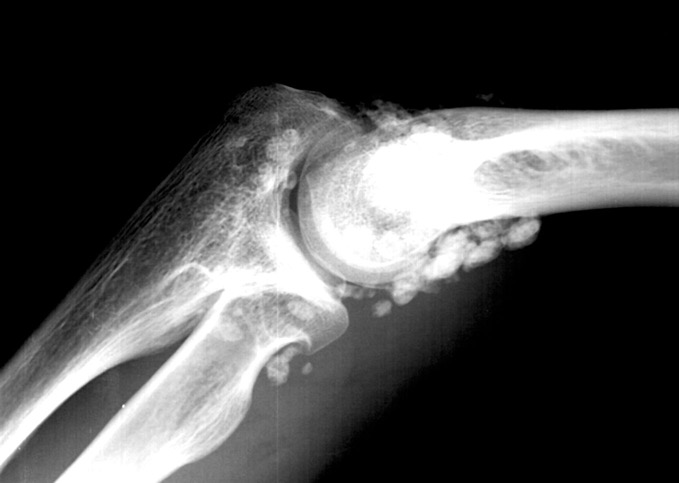

(Ostéo)chondromatose

Synovialopathie bénigne rare produit des nodules chondraux => libres => Ca++ => chondropathie => Arthrose précoce

RADIOGRAPHIE

Rarement vus